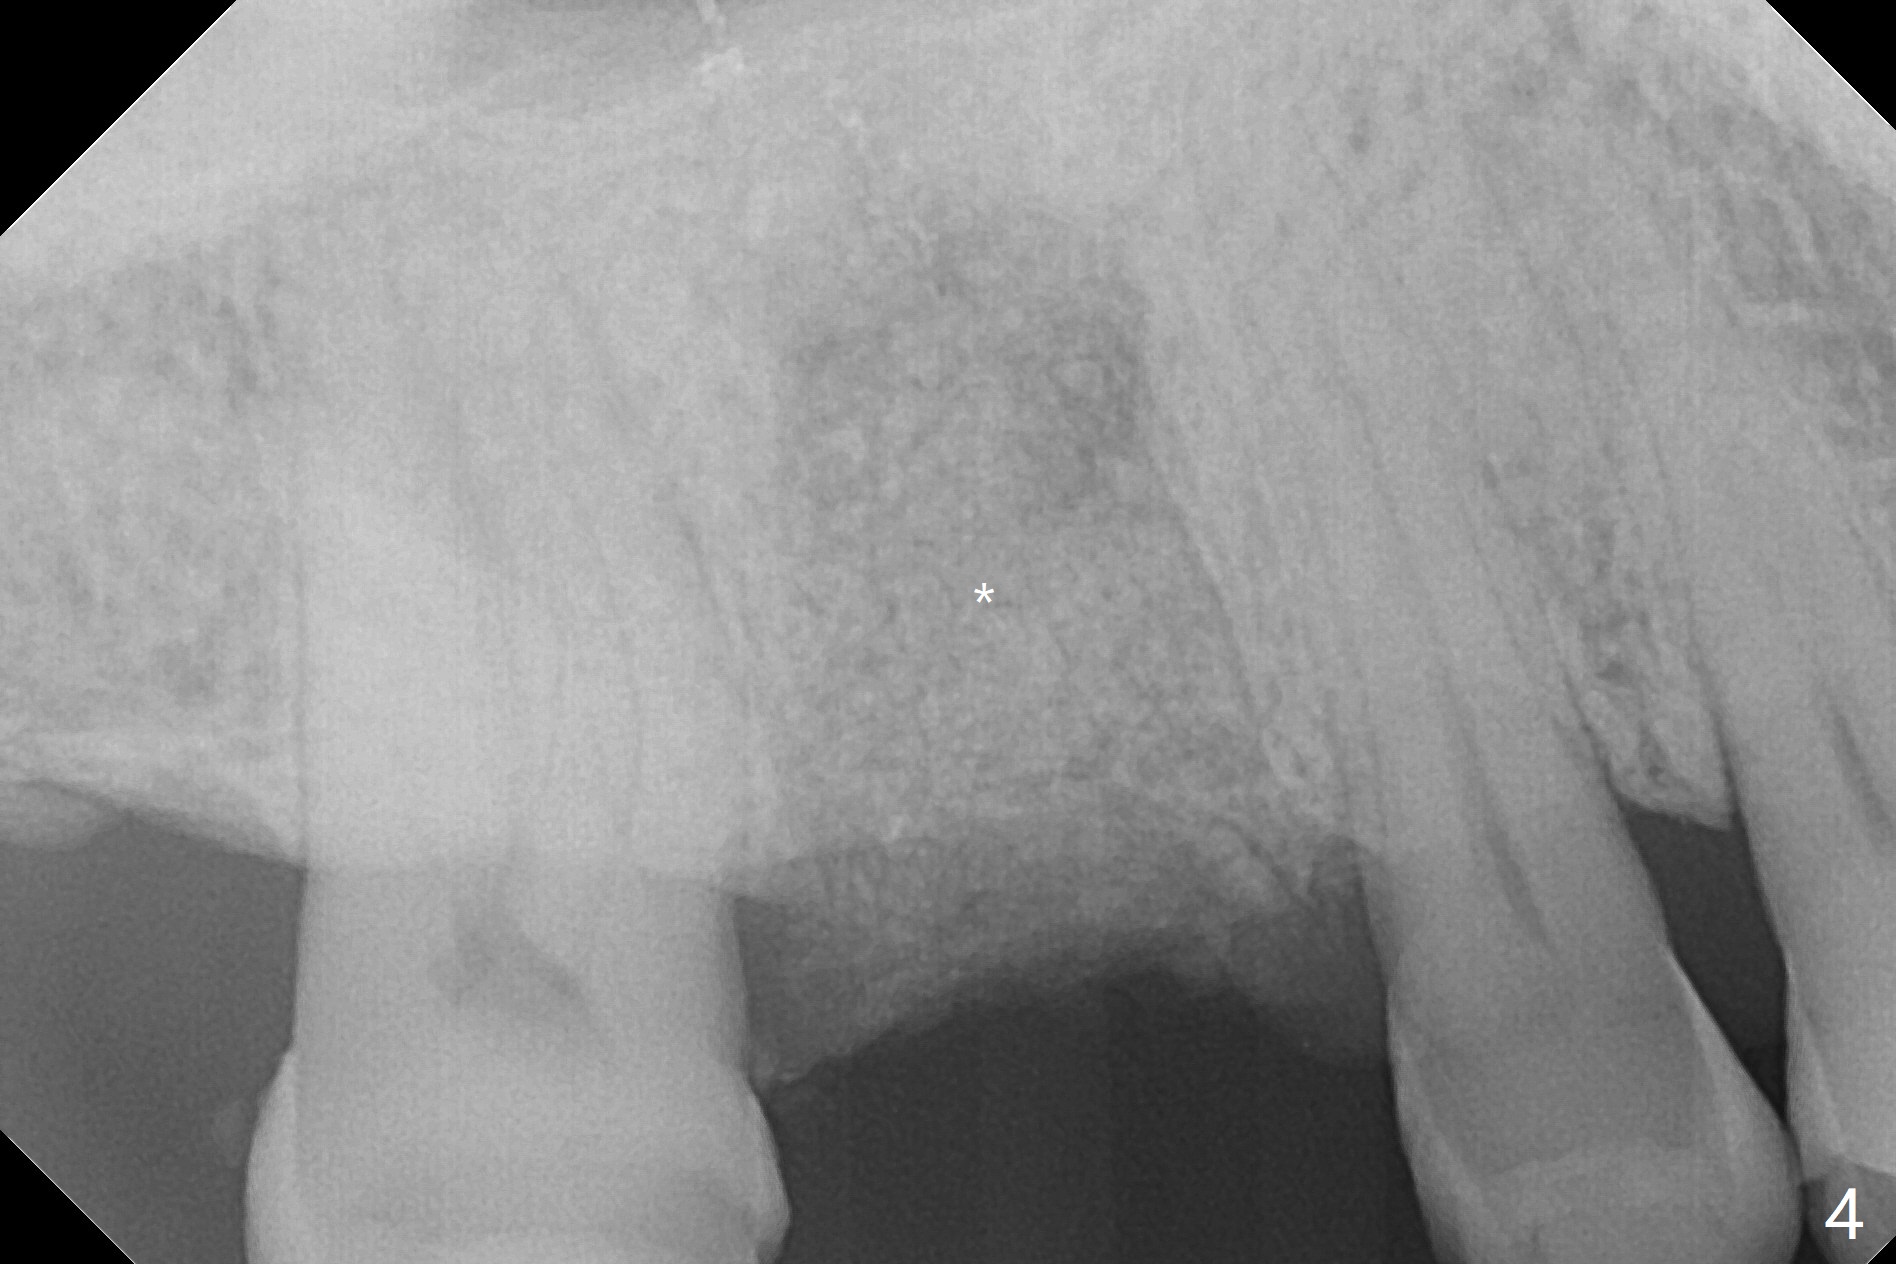

A 56-year-old man with signs of bruxism (multiple occlusal wear and tear, Fig.1) returns from an endodontist office because of failed RCT retreatment at #3 (Fig.2 (* palatal swelling; > fistula)). After difficult extraction, the socket is large without much septal bone (Fig.3 *). Because of lack of the apical native bone, immediate implant is not placed. If it has to be done, a large and long one is required. Instead socket preservation is finished (Fig.4 *). The socket is 20 mm deep, while the shank of surgical curettes is 20 mm. It appears that the most apical granulation tissue is hard to be removed. When 7-day oral Clindamycin is finished, the patient returns with chief complaint of recurrent pain and fistulae. In fact the palatal fistulae are flat without erythema. He returns asymptomatic 2 weeks postop; the fistulae are disappearing (Fig.5 ^) and the socket is healing (Fig.6).